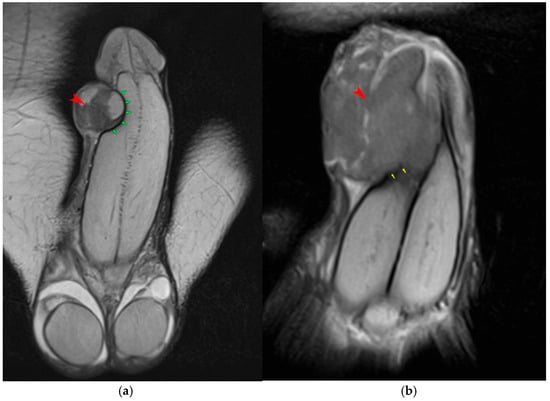

4.1. Penile Neoplasms

4.2. Penile Trauma